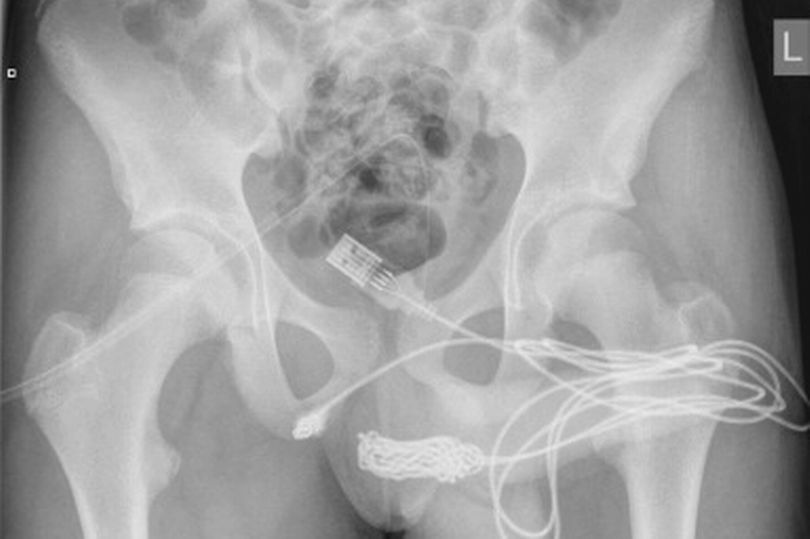

หลังจากการเอ็กซเรย์ (X-ray) ทำให้หมอและพยาบาลถึงกับผงะเพราะพบ สายไฟ USB ถูกสอดเข้าไปอยู่ในทางเดินปัสสาวะของเด็กชายทั้งหัว ทำให้เขาต้องเข้ารับการผ่าตัดในทันที

จากการสอบถามเด็กชายวัย 15 ปี เขาสารภาพว่านี่เป็นส่วนหนึ่งของการทดลอง วัดความยาวขององคชาตของเขา แต่การทดลองเกิดผิดพลาดเมื่อสาย USB ด้านหนึ่งไม่สามารถเอาออกมาได้ อีกทั้งสายภายในร่างของเด็กชายยังม้วนพันกันยุ่งเหยิงอีกด้วย